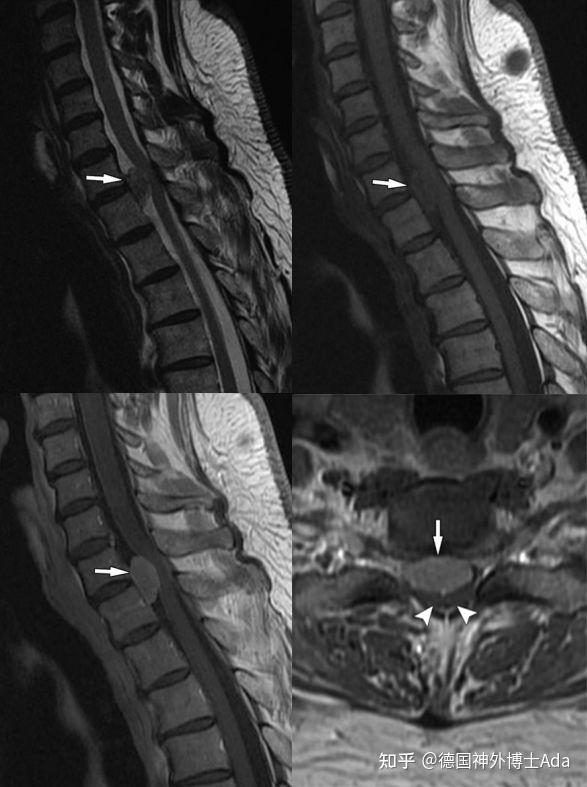

【经典】椎管内常见肿瘤mr诊断

髓外的良性肿瘤磁共振平扫:椎管内肿瘤压迫脊髓严重术中完整取出瘤体

椎管内硬膜下肿瘤影像特点及手术策略解析

六大椎管内硬膜下肿瘤影像特点及手术策略解析